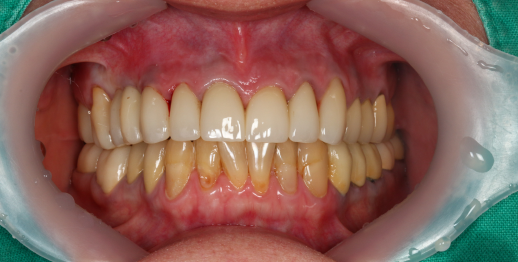

Upper jaw dental implants and bone graft

55 y.o, Russia

Operating dentist: Roh Hyun Ki